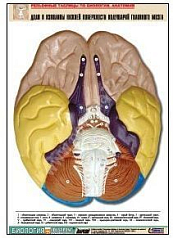

Комплект включает в себя 21 таблицу следующего содержания:

3. Доли и извилины нижней поверхности полушарий головного мозга;

Изделие соответствует Перечню средств обучения и воспитания, утвержденному Приказом Минобрнауки России N 804 (подраздел «Демонстрационные учебно-наглядные пособия для профильного медико-биологического класса»).